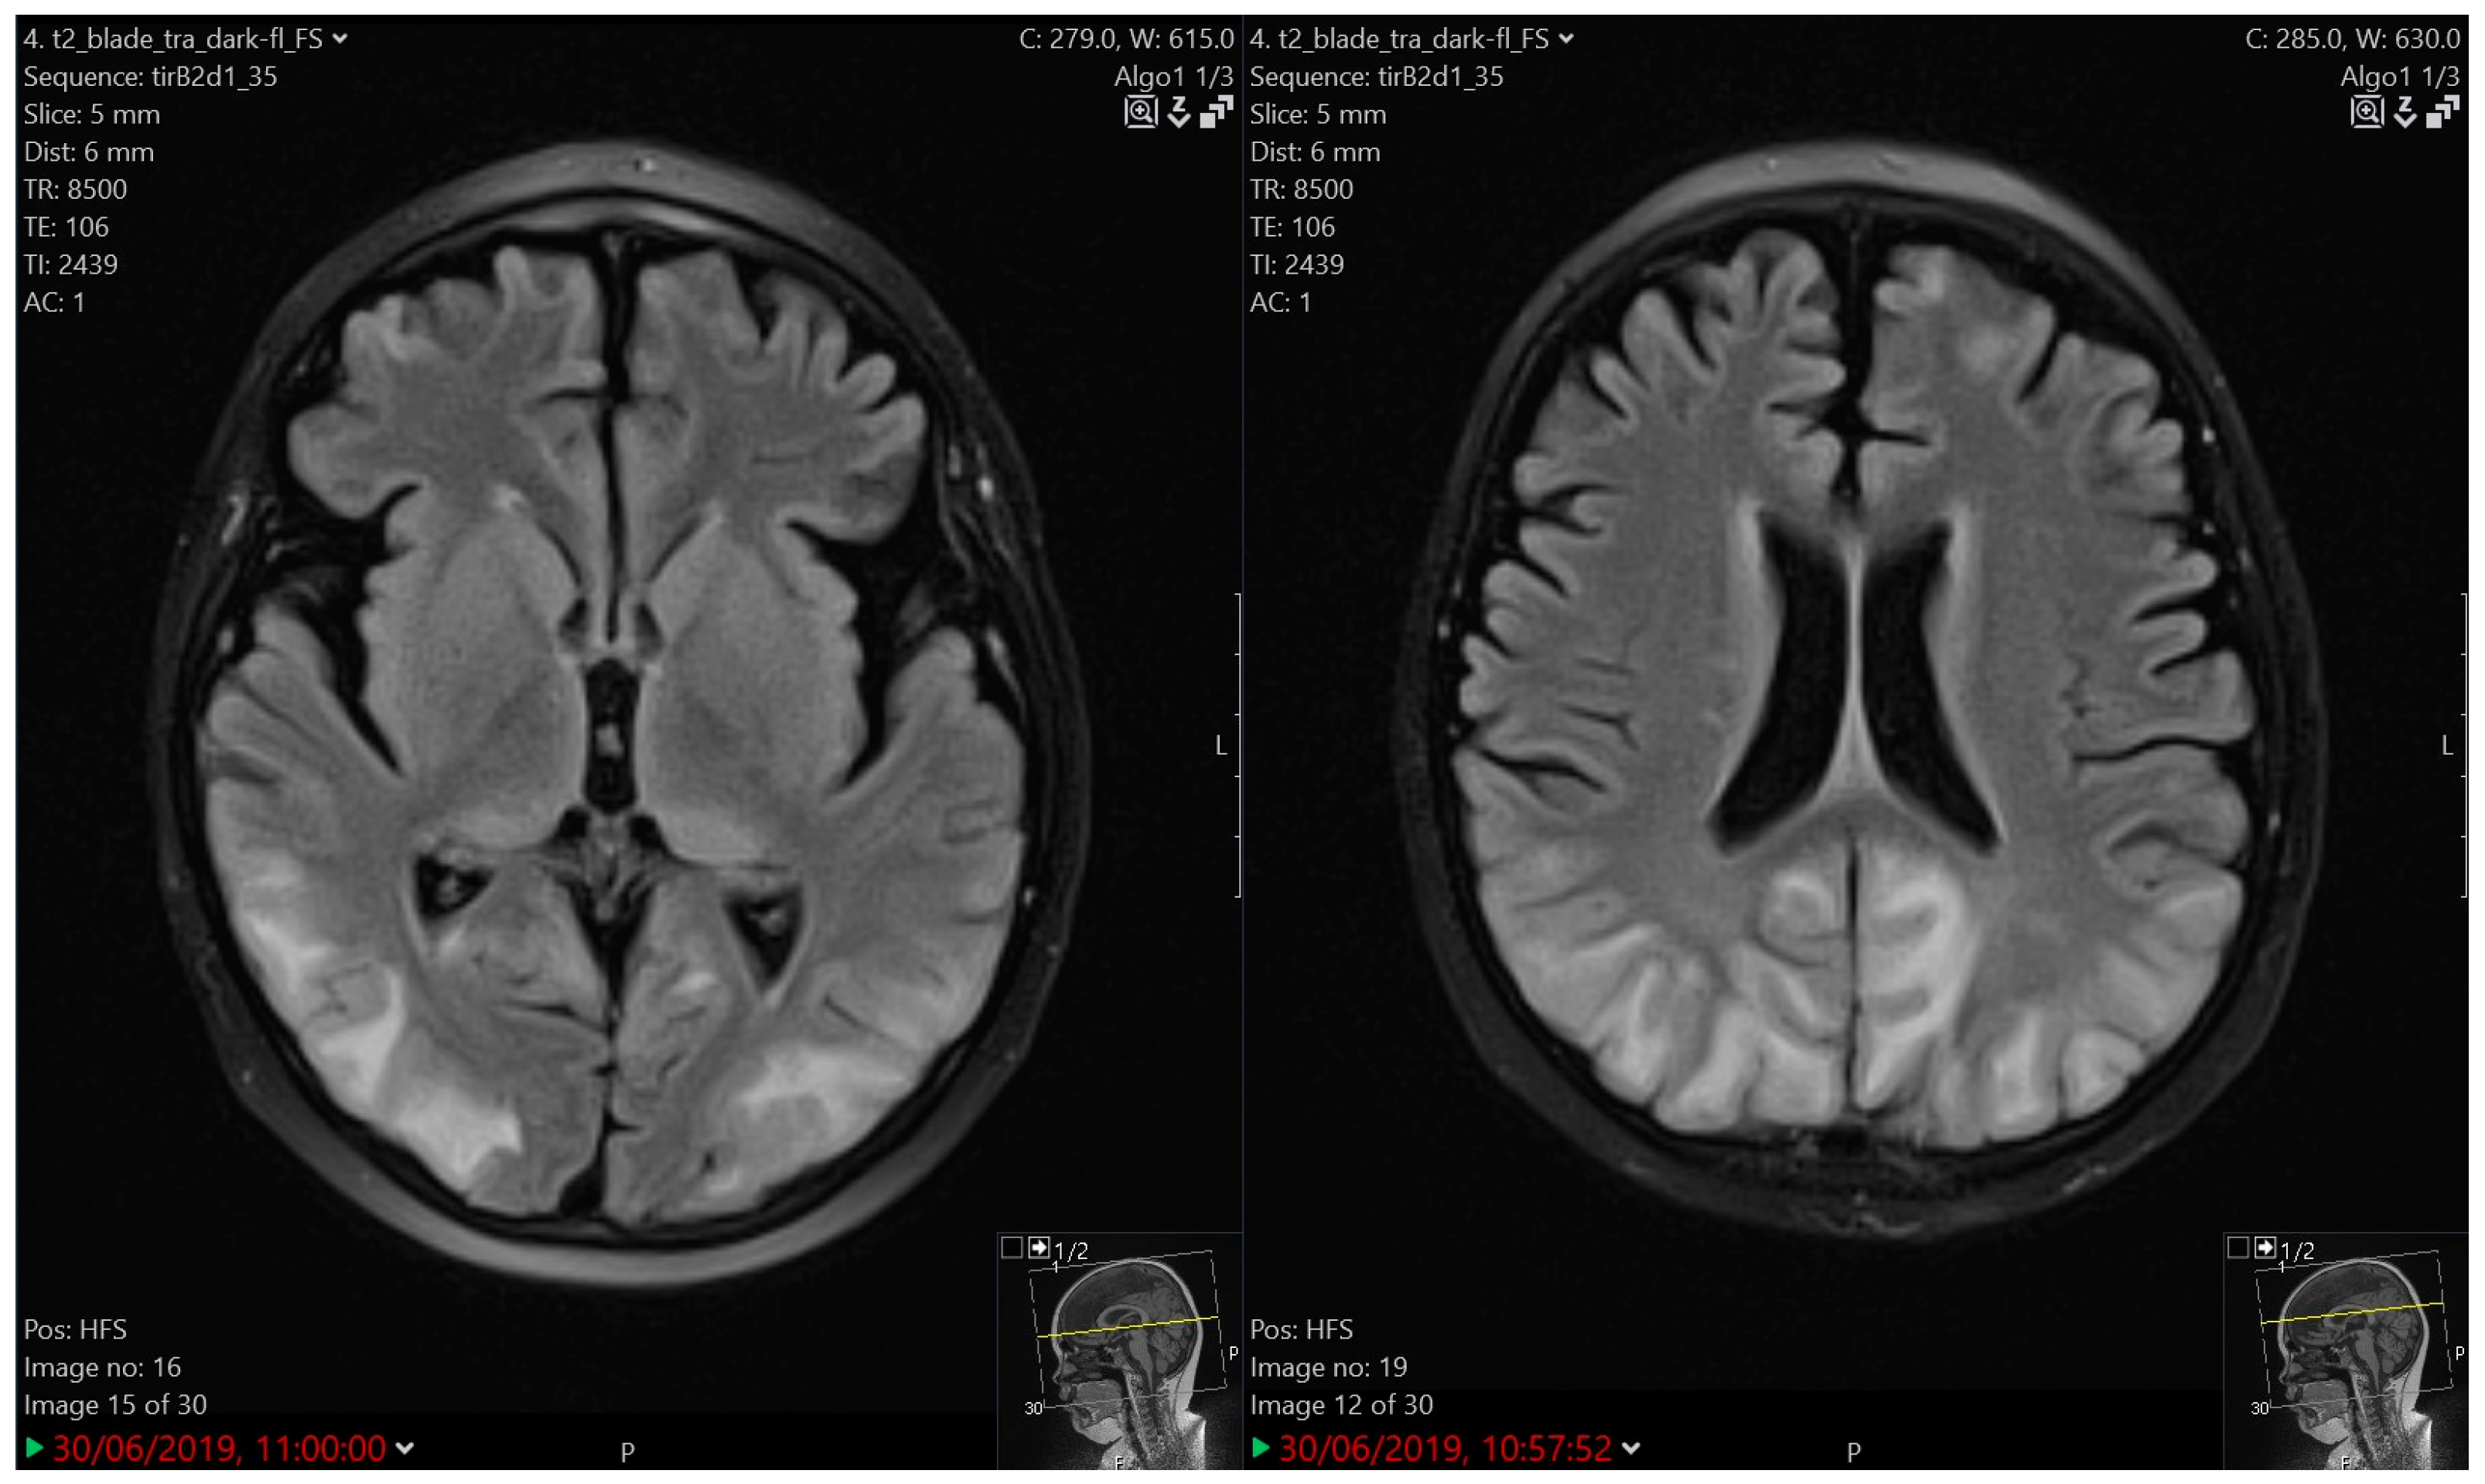

3.4.2. Imaging

| 3 | 7.5 | M | B | HR | Protocol II | Tonic-clonic seizure | 5 days | Very slow background activity | PRES | 3 | 1 year of AET, atrophic MRI brain changes |

| 4 | 7.5 | F | T | HR | Protocol IA | Atonic seizure, Subsequent right-sided hemiparesis | 2 days | Slower activity, high voltage slow waves left | Cerebro- vascular ischemia | 3 | Ongoing AET, atrophic MRI brain changes |

| 5 | 3.5 | F | B | HR | Protocol IA | Tonic status epilepticus | 10 min | Slower activity bilaterally | PRES | 4 | CR, atrophic MRI brain changes |

| 7 | 7.5 | F | B | IR | Protocol II | Tonic-clonic seizure | 30 s | Focal changes over FCT bilaterally with generalisation | LE | 3 | 5 years of AET; CTX modification |

| 8A | 6 | F | B | IR | Protocol II | Tonic seizure | 1 min | Slower activity CTP right | LE | 3 | Selective mutism |

| 8B | 10 | relapse | N/A | Protocol II-IDA | Complex partial seizure with generalisation; status epilepticus | 30 min | Focal changes left FCTO | LE, cortical oedema | 4 | 2 years of AET; ITT modification | |

| 9 | 3 | M | B | HR | Maintenance | Complex partial seizure with generalisation; status epilepticus | 2 h | Focal changes left | LE, pontine cavernoma, mineralising angiopathy | 4 | Two neurosurgical procedures; 5 years of AET |

| 11 | 4.5 | M | B | SR | Protocol II | Headache, vomiting | unknown | Not performed | LE, Chiari malformation type I | 2 | CR |